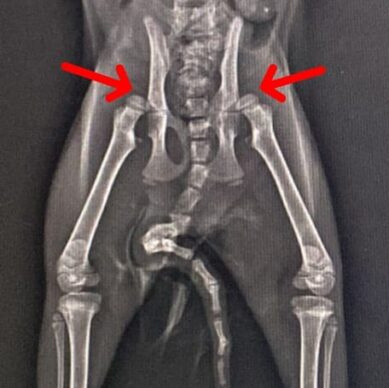

çıkık